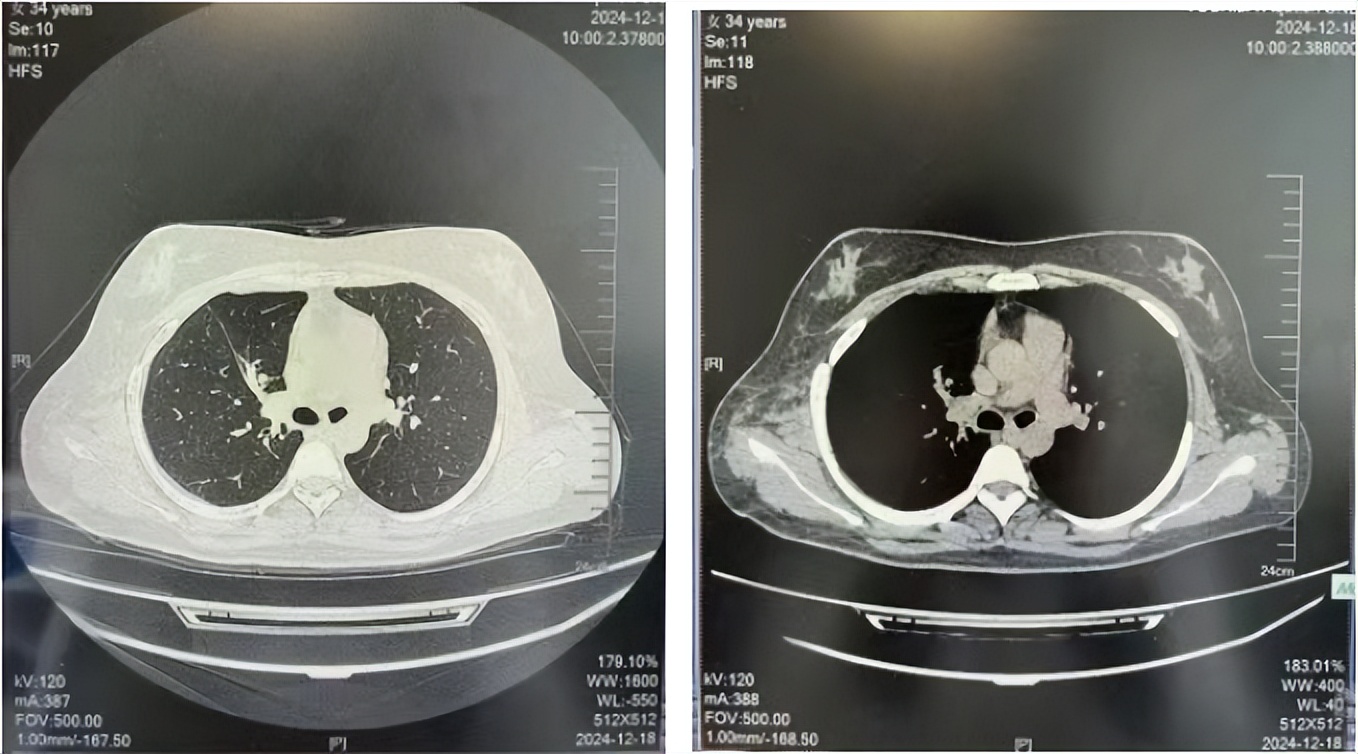

诊疗经过:2022年5月始口服克唑替尼3个月,出现肝功能异常(DILI 2级伴临床症状),改用恩沙替尼靶向治疗至今,目前评效为维持PR。恩沙替尼应用期间出现轻度肝功能异常(DILI 1级),对症处理后好转。截止目前PFS 33个月。

2023.05

2024.12